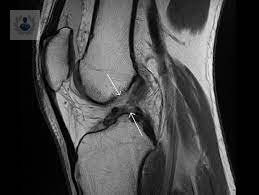

Lesiones de Meniscos: problema que afecta el día a día

Una Lesión de Menisco es una rotura de una o más de las tiras de fibrocartílago en forma de C que se encuentran en la rodilla.